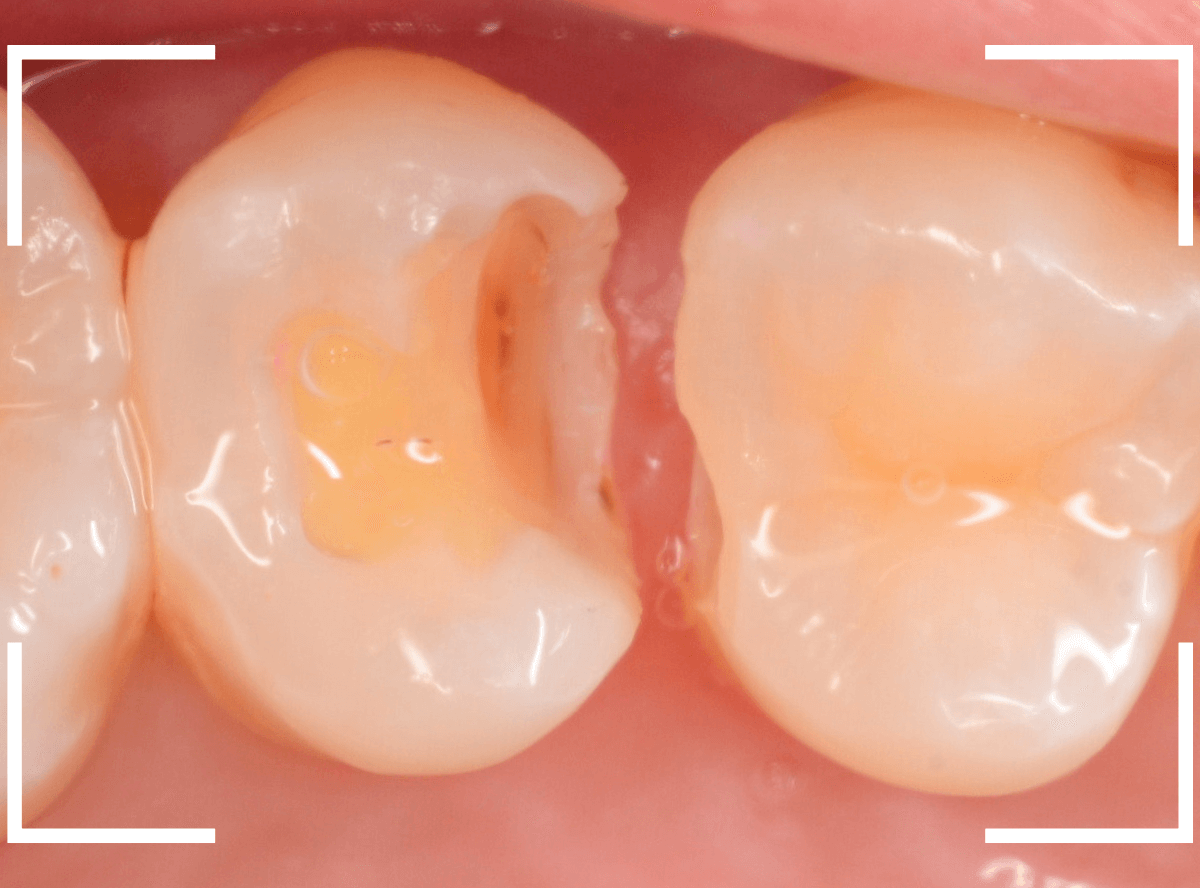

Case.28 虫歯治療後、半年以上来院されなかった患者さん

虫歯を治療して、セメントで歯を削った部分を封鎖した後、再修復を検討中で、半年以上来院されなかった患者さんです。

虫歯を治療して、セメントで封鎖した状態というのは、家でいえば、しっかりした屋根がない状態です。

今回は、セメントの一部がはがれる程度で済んでいましたが、虫歯が再発し、再治療、最終修復物の変更の可能性も出てきます。

皆さんも治療は中断せずに最後まで通院するようにしてくださいね。

治療再開後、セラミックの最終修復を希望されましたので、歯をトリミングし、型取りします。